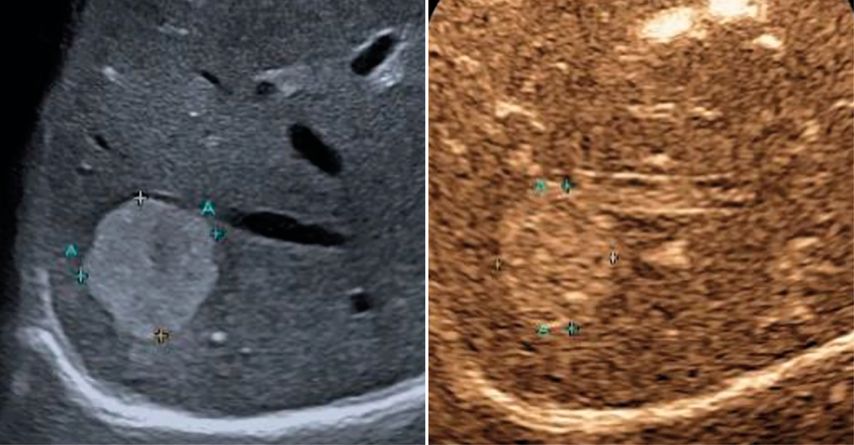

Trotz der hohen Aussagekraft moderner Ultraschallgeräte im B-Mode kann derzeit – mit Ausnahme des Screenings auf hepatozelluläre Karzinome bei chronischen Lebererkrankungen – kein generelles Leberscreening empfohlen werden.5 Die Mehrzahl fokaler Leberläsionen ist benigne, darunter fokale Steatosen, Zysten, Hämangiome oder fokale noduläre Hyperplasien (Abb.3). Maligne Raumforderungen sind in populationsbasierten Studien selten.6

Abb. 3: Darstellung einer fokalen nodulären Hyperplasie (FNH) in der arteriellen Frühphase nach Gabe von 1,2ml SonoVue® mittels CEUS (links) und in der mikrovaskulären Bildgebung (Canon®-superb «Microvascular imaging»-Modus), wo die Radspeichenstruktur besser zur Darstellung kommt